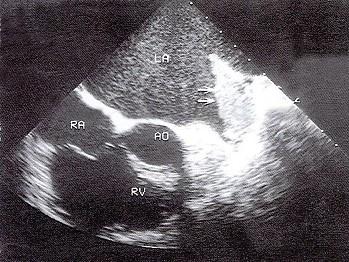

该食管超声心动图箭头所示为?(?)A.左心耳血栓B.左房黏液瘤C.左房梳状肌D.以上都不是E.左房赘生物

问题 该食管超声心动图箭头所示为?(?)

选项 A.左心耳血栓 B.左房黏液瘤 C.左房梳状肌 D.以上都不是 E.左房赘生物

答案 A